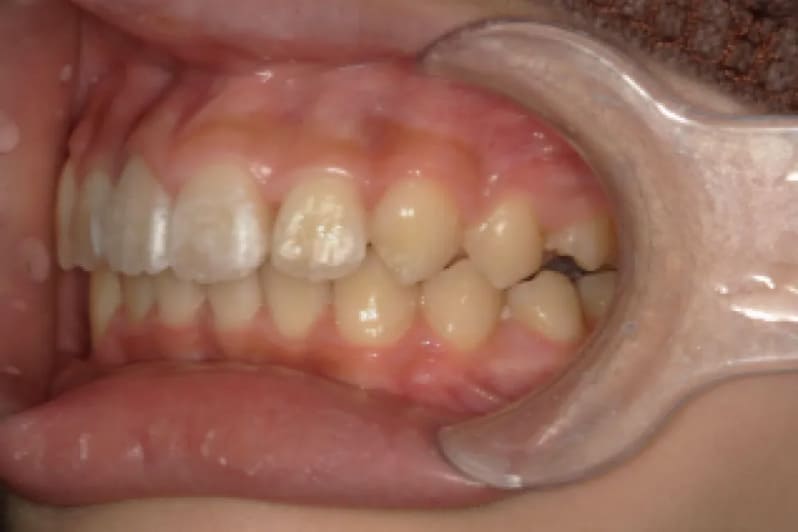

| Before | ![]() |

| 性別 | 男性 |

| 年齢 | 小学校高学年 |

| 治療費用 | 902,000円 |

| 治療期間 | 1年9か月 |

| 治療内容 | マウスピース矯正 |

| リスク 副作用 |

矯正治療の一般的なリスクといたしましては、治療中のお痛み・歯根吸収・歯肉退縮・治療後の後戻りなどが生じる可能性があります。矯正治療は始めると、元の状態に戻すのが難しいことがあります。 |